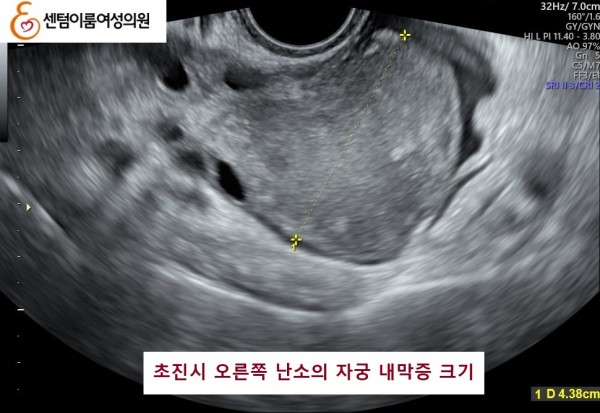

2025.6.28 본원에 내원시 양측 자궁 내막종이오른쪽 4.5cm , 왼쪽 1.3cm 정도 였습니다.

본 원에서 수술없이 알콜경화술 3개월 후 양측 다 사라진 사례입니다.